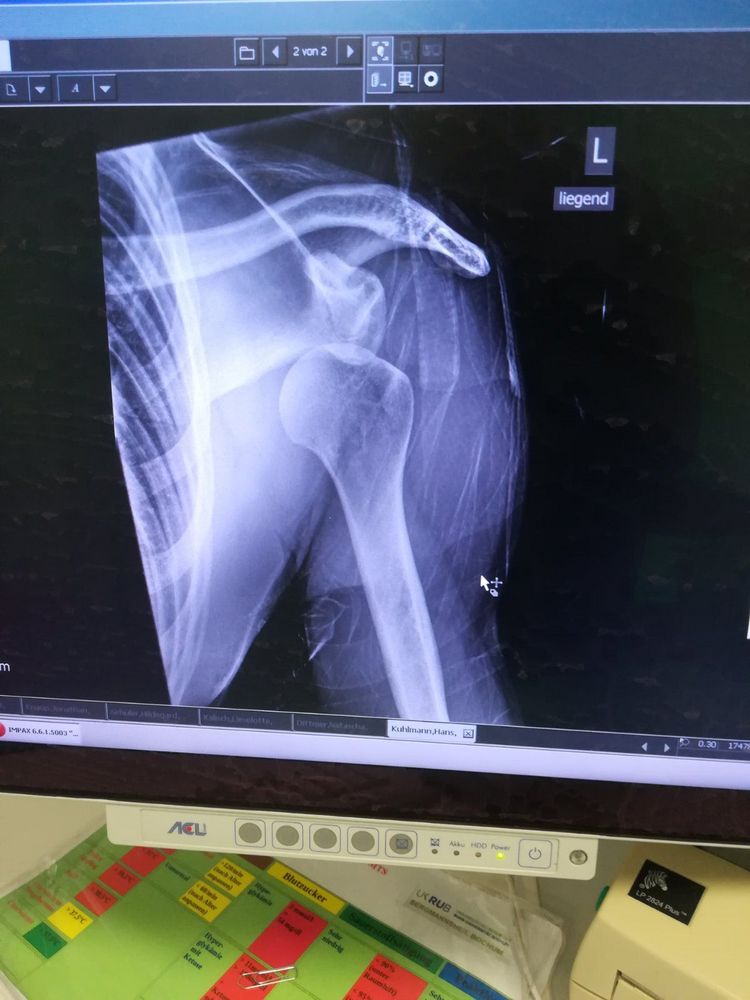

My Shoulder Dislocation & useful links and information on recovery 🦾

How I dislocated & rotator cuff exercises link I have been working out regularly 4 times a week for over